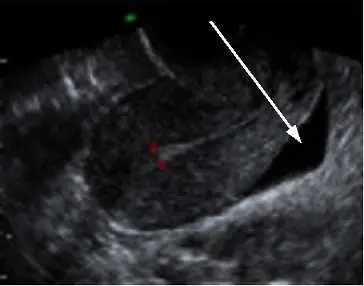

下圖為骨盆腔超音波影像,其中箭號所指的構造為何?

本題考查骨盆腔超音波(pelvic ultrasound)中女性骨盆腔的重要解剖隱窩(recess)識別,特別是 cul-de-sac(直腸子宮陷凹,又稱 Douglas 窩/pouch of Douglas)的超音波影像特徵。

本張骨盆腔超音波影像(應為經腹部或經陰道掃查)顯示女性骨盆腔矢狀切面。影像中可見:

- 中間偏左有一呈中等回音的實體構造(子宮)

- 右上方箭號所指位置呈現一個楔形或三角形的無回音(anechoic)液體聚積區,位於子宮後壁與直腸前壁之間的空間

- 此無回音區的位置、形態與分佈符合 cul-de-sac(直腸子宮陷凹)少量游離液體之超音波表現

Cul-de-sac 是女性腹膜腔最低點,即使少量腹腔游離液(如排卵後生理性積液)也會優先積聚於此,超音波下表現為子宮後方的無回音帶或三角形液體區。